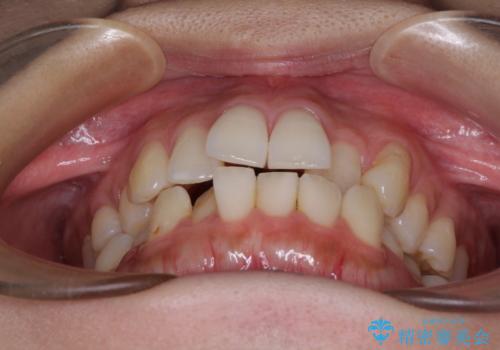

- 上下前歯のデコボコを気にして来院された患者様です。

上顎歯列が下顎の歯列に対して狭小であり、一部下顎の奥歯が上顎よりも外側に位置している状態でした。

上顎の急速拡大装置を使用して上顎骨を側方に拡大することで上顎歯列を拡大し、下顎歯列も拡大できるようにすることで、歯列を整えることとしました。

上顎の拡大は、左右どちらに拡大していくのか予想が困難ですが、こちらの患者様では結果として上下正中が一致する方向に拡大され、非常にきれいな仕上がりとなりました。